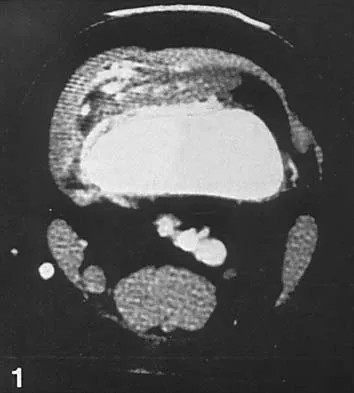

A 26-year-old woman sustained a nondisplaced femoral neck fracture and treatment consisted of use of percutaneous cannulated screws. At her 3-month follow-up visit, she reports hip pain and is unable to ambulate. A radiograph is shown in Figure 1. What is the next most appropriate treatment?

Explanation

Femoral neck fracture nonunion is a challenging problem for orthopaedic surgeons. Vertical fractures are more prone to nonunion due to shear stress rather than compressive forces across the fracture site. Several authors have suggested these fractures are more common in young adults due to injury type and bone composition. It is widely regarded that an effort should be made to salvage the femoral head if vascularity remains. The most common method to treat this complication is valgus intertrochanteric osteotomy of the femur. This functionally makes a vertical fracture more horizontal, converting shear into compressive forces. It also helps correct the varus position of the fracture nonunion. Hartford JM, Patel A, Powell J: Intertrochanteric osteotomy using a dynamic hip screw for femoral neck nonunion. J Orthop Trauma 2005;19:329-333.